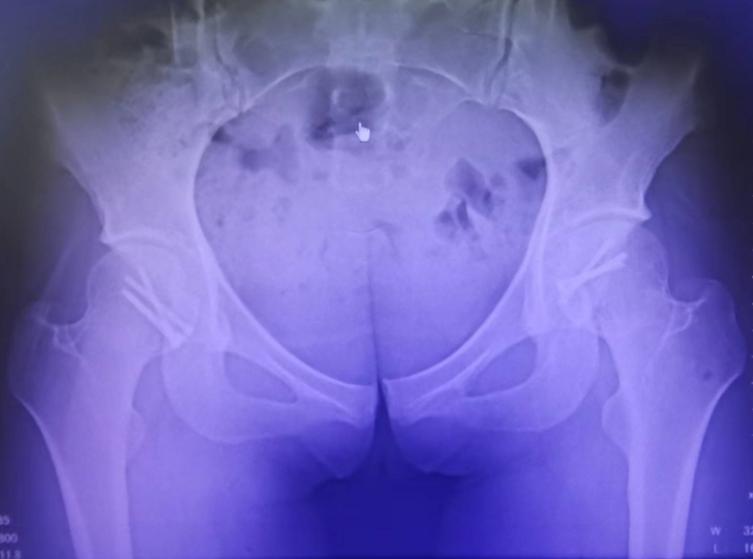

术后影像学资料

术后1年